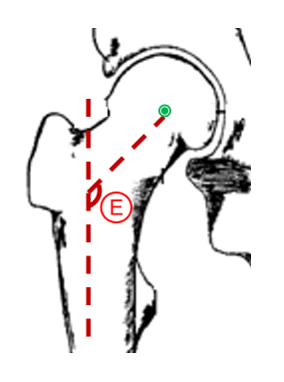

This red line represents

Answer

• Kohler's Line

• Skinner's Line

• Whiteside's Line